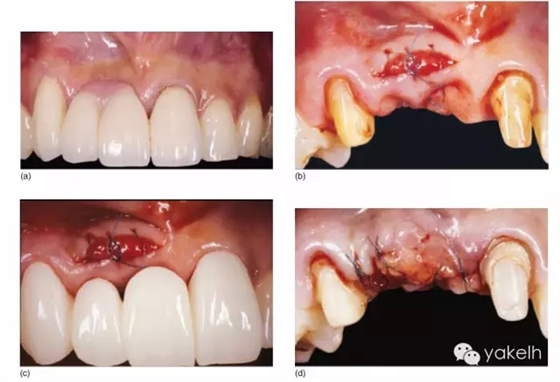

¤¤這類復(fù)雜的膜齦手術(shù)用于同時(shí)處理多個(gè)根面Ⅰ類/使Ⅱ類牙齦退縮(圖5.11a~m)。

圖5.11 (a)患者休息放松狀態(tài)下的嘴唇——上下唇不能完全閉合。(b)右上尖牙和側(cè)切牙呈Ⅰ類牙齦退縮。(c)左上頜尖牙和側(cè)切牙呈Ⅱ類牙齦退縮。(d)先用圓形眼科刀片開始做溝內(nèi)切口。(e)使用探針在袋內(nèi)垂直探查貫通隧道,越過膜齦聯(lián)合。(f)使用探針在隧道內(nèi)橫向探查貫通,保留齦乳頭尖端附著于骨面。(g)從腭部取結(jié)締組織移植物,使用絲線牽引,將厚度和大小足夠的結(jié)締組織瓣插入隧道內(nèi)。(h)通過懸吊縫合將組織瓣冠向復(fù)位,穩(wěn)定結(jié)締組織瓣。(i)術(shù)后6個(gè)月,上頜右側(cè)觀。(j)上頜左側(cè)觀,可見牙齦厚度以及色澤的協(xié)調(diào)性均得到改善。(k)術(shù)后6個(gè)月正面觀,牙敏感癥狀消失。(l)術(shù)后1年的全口影像,顯示雙側(cè)的牙齦退縮均被完全覆蓋,牙齦邊緣增厚且穩(wěn)定,與釉牙骨質(zhì)界輪廓一致,也與左側(cè)中切牙釉質(zhì)缺損輪廓一致。(m)患者嶄新的笑容,可見側(cè)切牙及尖牙的齦緣無退縮。